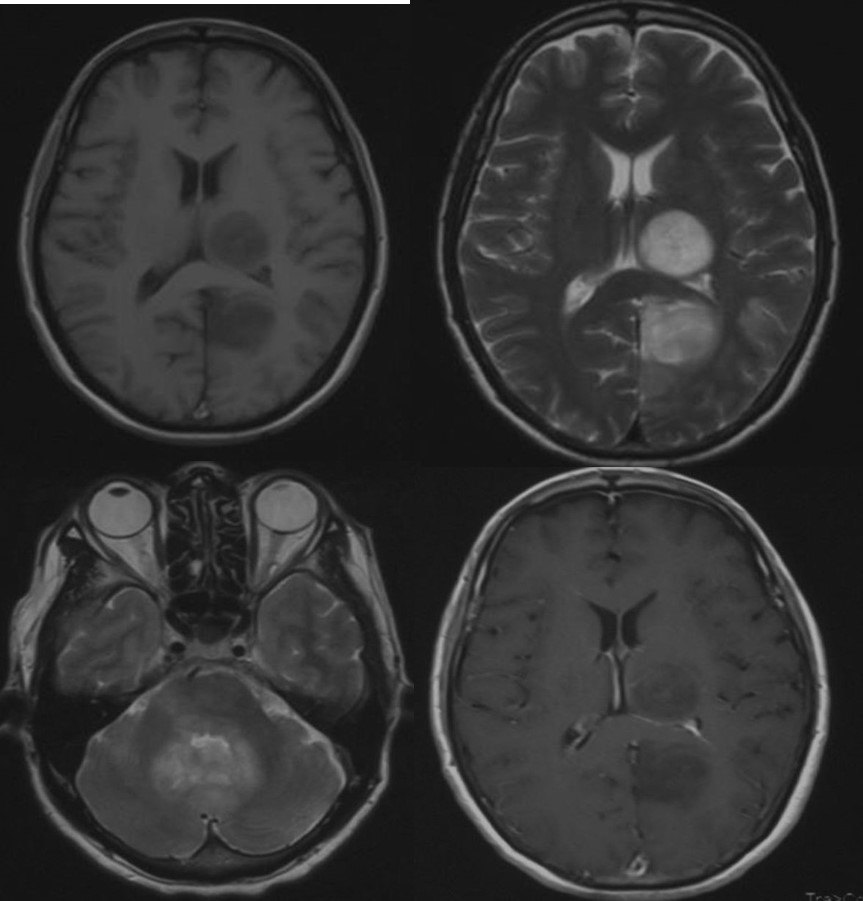

该患者男,19岁,因头痛头晕1个月前来就诊。头颅MRI示:幕上、幕下多发病变。术前诊断:转移瘤?淋巴瘤?行右侧颞叶脑立体定向活检术,病理提示:中枢胚胎性肿瘤。

中枢神经系统胚胎性肿瘤指有未分化或低分化的神经外胚层细胞形成的高度恶性的肿瘤,具有多向分化的潜能。该病比较少见,占中枢神经系统肿瘤的0.1%,好发于儿童和青少年。该病预后不良,明确诊断仍然依靠手术或活检。